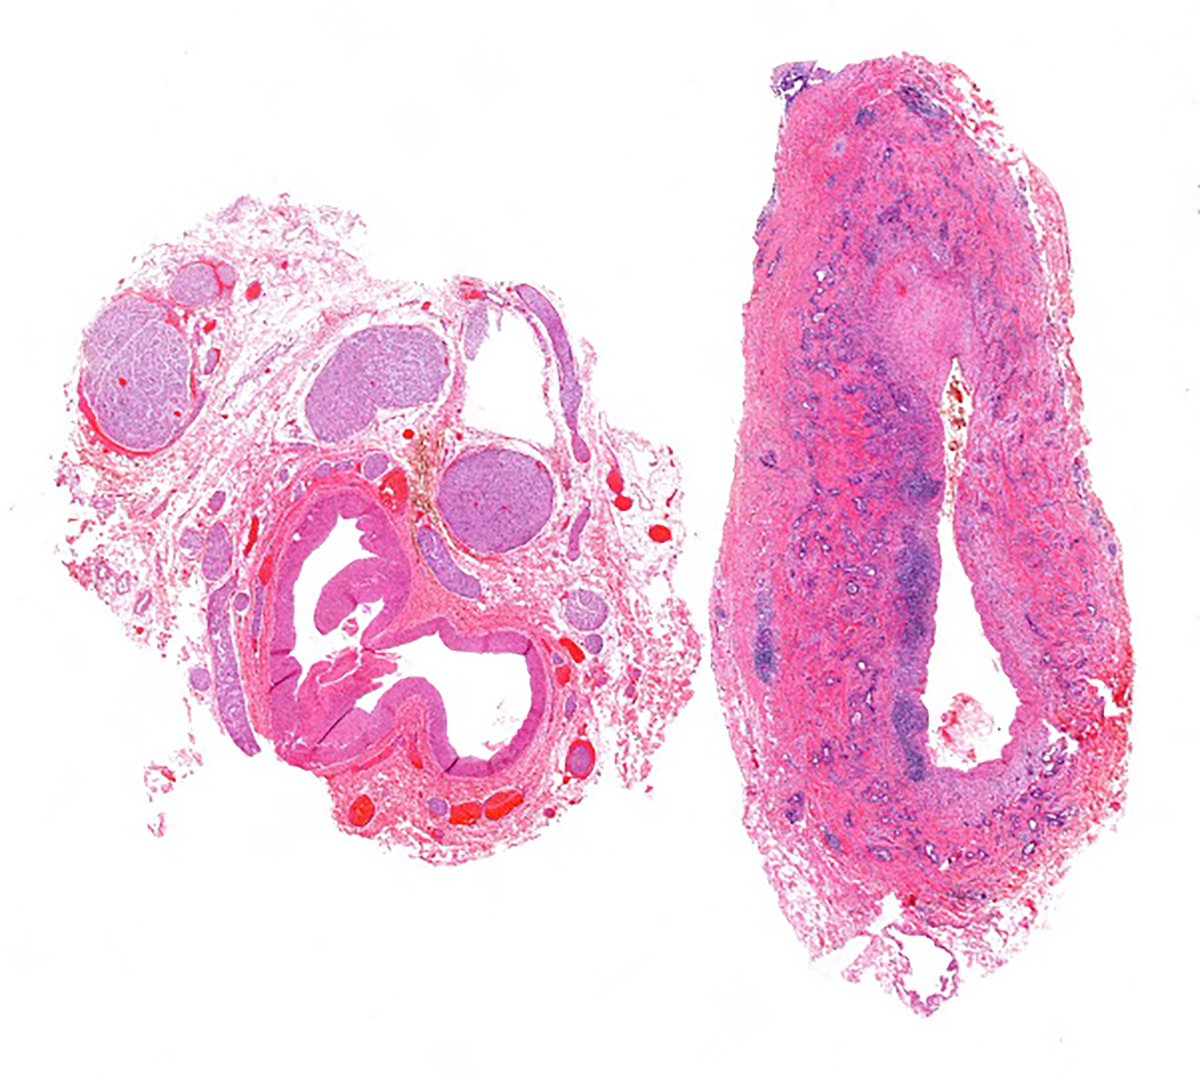

Appendectomy specimen. High-power image. What do folks think the diagnosis is? #pathology #gipath #PathTwitter